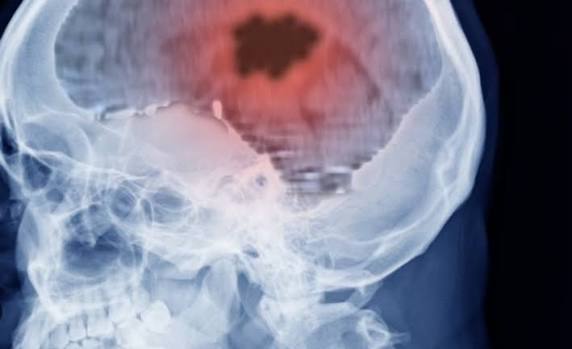

وأفاد الباحثون، أنه يعتمد تشخيص الزهايمر حاليًا على: فحوصات دماغية باهظة التكلفة، وتحاليل السائل النخاعي (البزل القطني) شديدة التدخل

وأشار الباحثون، إلى أن الزهايمر يتميز بتراكم بروتينين في الدماغ: الأميلويد، التاو، وبروتين p-tau127 يُعد من أدق المؤشرات الحيوية في الدم

يعكس وجود كلا البروتينين في الدماغ، وكلما تقدم المرض، زادت مستويات البروتين في الدم.